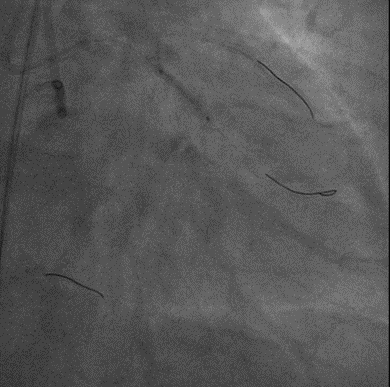

手术影像

左冠优势,LM、LCX未见狭窄,TIMI3级;LAD近段CTO,TIMI0级

RCA细小,近中段狭窄40%-50%,TIMI3级;远端可见LAD侧枝血流

策略讨论:近端纤维帽不清晰,LAD中段显影可见,闭塞段长度>20mm。间隔支逆供条件尚可。CTA提示LAD多发钙化。尝试正向开通,优选亲水性滑导丝,若失败,及时调整逆向策略。